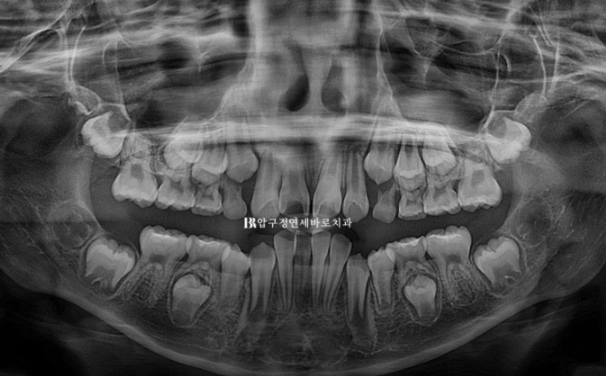

엑스레이를 보면 아직 유치가 8개나 남아있긴 합니다만 보증기간인 18개월 후면 영구치도 대부분 나올 것으로 예상이 됩니다.

악궁확장을 통해 영구치 맹출공간 확보, 윗니 돌출 해소, 앞니 배열을 목표로 장치 제작에 들어갔습니다

뿌리 평행도 역시 좋습니다.